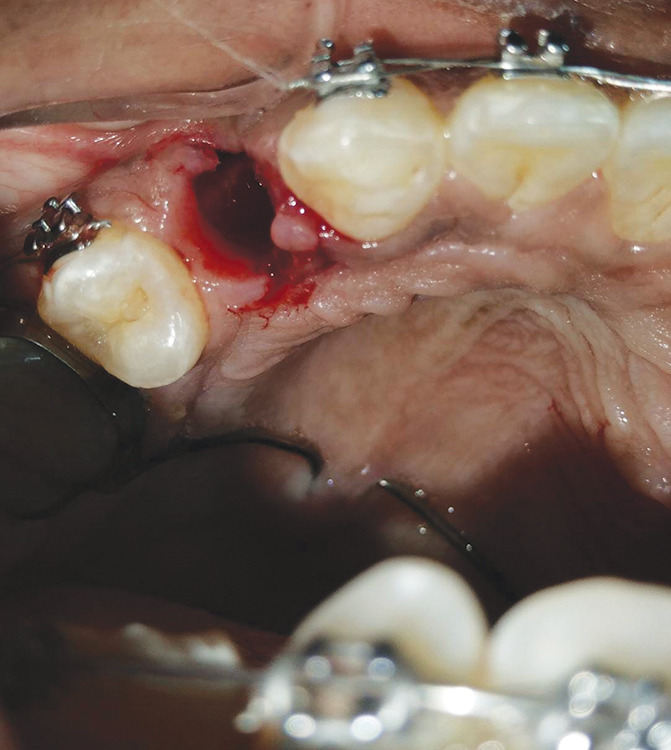

Materials and methods: A prospective split-mouth, in vivo study was conducted on 13 patients requiring bilateral premolar extractions for orthodontic treatment. A-PRF was applied to the extraction site on one side (study group), while the contralateral side served as a control. Mini screws were placed bilaterally to facilitate canine distalization using NiTi closed-coil springs with 150 gm of force. Clinical wound healing was evaluated on days 3 and 7 postextraction, while orthodontic tooth movement was measured monthly using digital calipers over a four-month period. Data were analyzed using Mann-Whitney U and Chi-square tests.